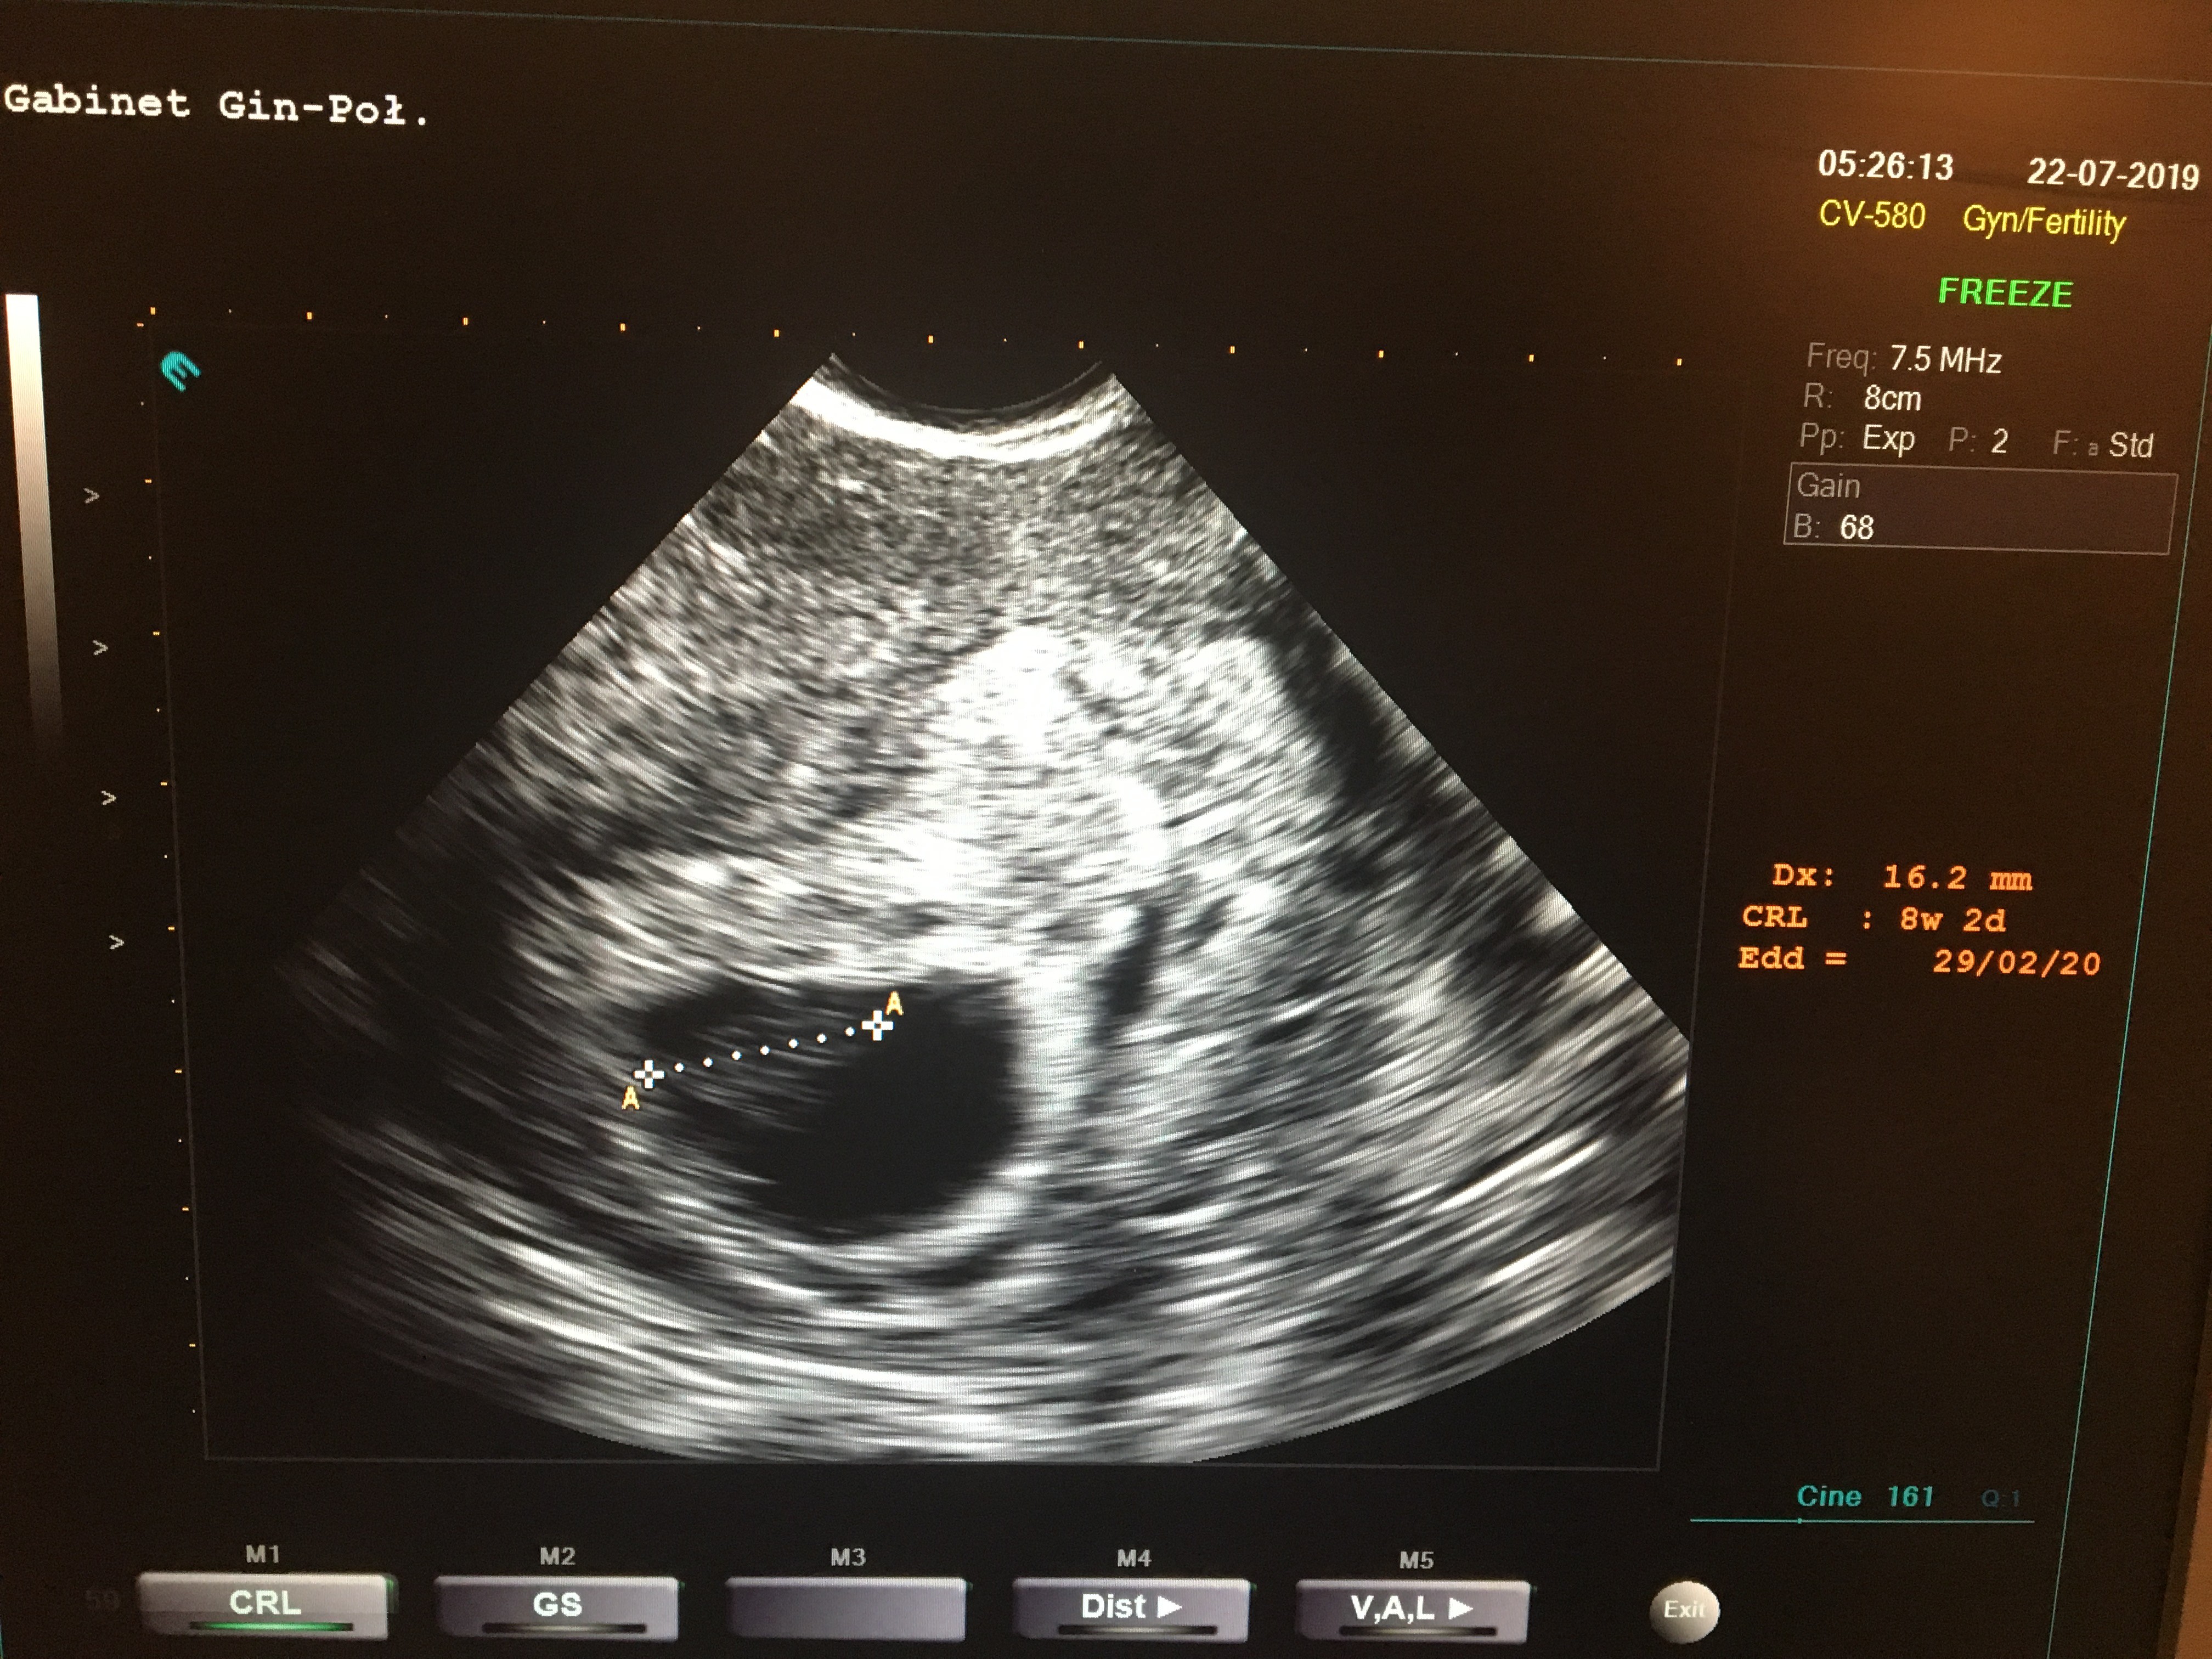

to mój miał w 7tc 1dz dokładnie 10,5mmJa juz tez po. Wszystko ok. Moj bąbel ma 16,2 mm serduszko bije ❤Następna wizyta 12.08. Dostałam dalej duphaston.

Jako duży i ślicznyJa juz tez po. Wszystko ok. Moj bąbel ma 16,2 mm serduszko bije ❤Następna wizyta 12.08. Dostałam dalej duphaston.

Ja juz tez po. Wszystko ok. Moj bąbel ma 16,2 mm serduszko bijeNastępna wizyta 12.08. Dostałam dalej duphaston.